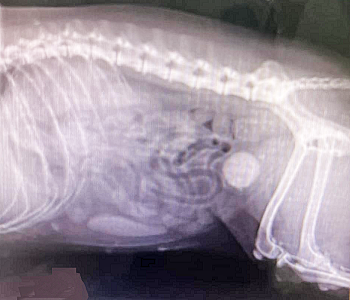

In addition to the customary bodily examination and observation of

symptoms, diagnosis is determined by

blood and urine analyses,

x-ray (see light round object in x-ray at right), urinary

untrasounography, and retraction of the stones by urinary cathether and

repeated flushing, aspiration, and bladder agitation to retrieve the

stones for microscopic analysis. Urine typically would include

inflammatory urine sediment, including pyuria (white blood cells),

hematuria (red blood cells), and proteinuria (unusually high amounts of

protein).